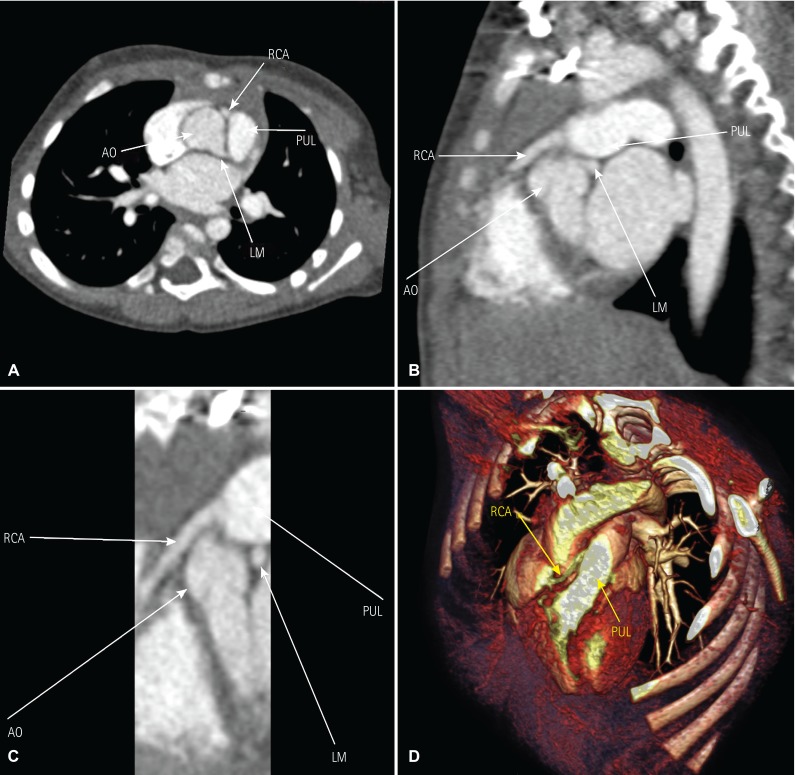

Patient no.2 was an 18-month-old male with a weight of 9.8 kg who was asymptomatic; during a routine checkup a 2/6 systolic murmur was heard in the left second intercostal space, ECG was normal. However, TTE demonstrated a dilated left coronary artery (0.3 cm diameter) and normal left and right ventricular function without any associated lesions. CTA revealed an RCA originated from the right side of the PA with an anterior course in relation to the ascending aorta along with a right dominant coronary system (Fig. 1). The patient underwent reimplantation of the anomalous RCA into the ascending aorta, with the origin of the RCA from the right facing sinus of the PA adjacent to the commissure. The patient was weaned off the CPB without inotrope support. In the ICU Milrinone with a dose of 0.5 mcg/kg/min was administered along with unfractioned Heparin infusion with a dose of 100 units/hour. The intubation time lasted 26 hours and the patient was discharged after 6 days on aspirin and furosemide. At the one-year follow-up, the patient was asymptomatic (no chest discomfort or dyspnea) with a LVEF of 66% measured by TTE.

Fig. 1. Preoperative diagnostic images of the anomalous right coronary artery. (A) Computed tomographic angiography showing the anomalous right coronary artery originating from the pulmonary artery in coronal view, (B) sagittal view, (C) zoomed view, and (D) three-dimensional view. RCA: right coronary artery, AO: aorta, PUL: pulmonary artery, LM: left main coronary artery.